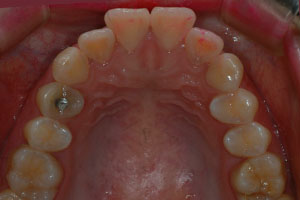

치료증례 전후사진

Before & After